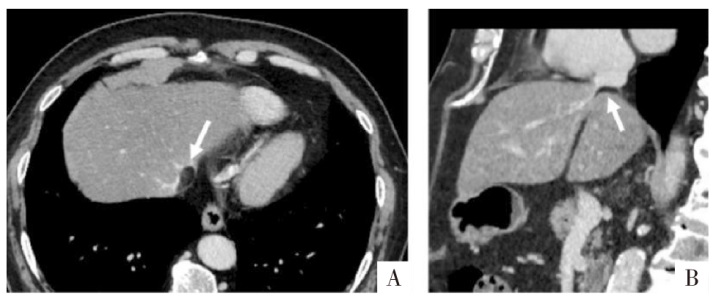

图14

病人男,45岁,下腔静脉旁假性脂肪瘤。A图,CT横断面显示似下腔静脉内充盈缺损(箭头);B图,矢状面多平面重组显示脂肪组织位于下腔静脉旁,挤压下腔静脉(箭头)。